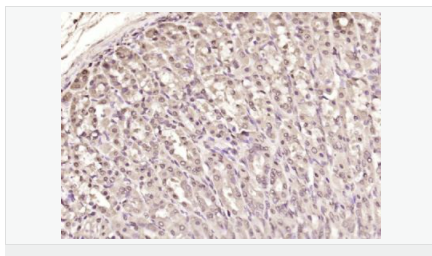

交叉反應:Human,Mouse,Rat(predicted:Pig,Cow,Rabbit,Sheep) 推薦應用:WB,IHC-P,IHC-F,IF,Flow-Cyt,ELISA

| 產(chǎn)品應用 | WB=1:500-2000 ELISA=1:5000-10000 IHC-P=1:100-500 IHC-F=1:100-500 Flow-Cyt=1μg/Test ICC=1:100 IF=1:100-500 (石蠟切片需做抗原修復) not yet tested in other applications. optimal dilutions/concentrations should be determined by the end user. |